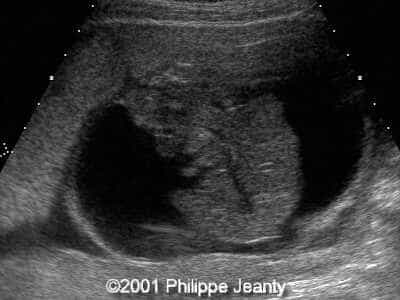

This 2nd trimester fetus has the following images (actually, these images remained unchanged for several weeks)

The findings are:

• very enlarged lungs on both sides

• inversion of the diaphragm that is convex towards the abdomen

• small compressed heart

• ascites but no generalized hydrops (no skin thickening for instance)

A much more common diagnosis for a bilateral echogenic lung associated with microcardia and ascites (Budd-Chiari phenomenon) is Larynx, atresia or as reported by several the CHAOS syndrome which stands for Congenital High Airway Obstruction Syndrome (which is typically laryngeal or tracheal atresia). This is the diagnosis that was indeed suspected in this fetus.